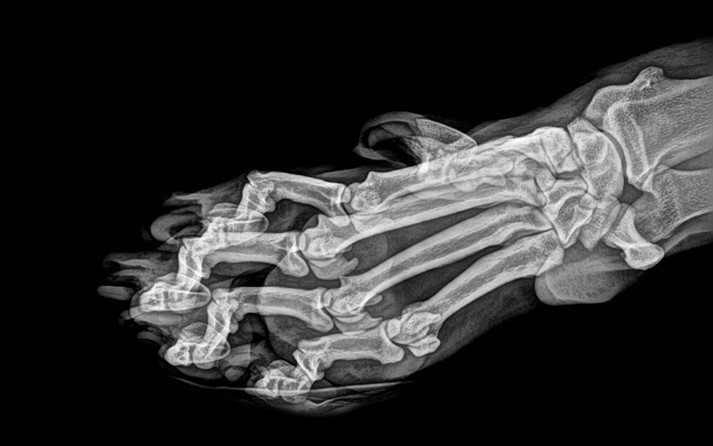

Зоопарк города Портленд (Орегон, США) решил порадовать любителей животных необычной «фотосессией» по случаю Хеллоуина – на своем сайте он опубликовал рентгеновские снимки своих постояльцев.

В подборку попали еж, хамелеон, фламинго, амурский тигр, летучая мышь, черепаха и многие другие.

На самом деле эксперимент был сделан не только для красоты. Цифровая рентгенография позволяет работникам ветеринарной медицины получать рентгеновские результаты быстрее и точнее настраивать изображение после их получения, а следовательно - минимизировать анестезию и время осмотра животных.

Каждое животное в зоопарке штата Орегон проходит обычный медицинский осмотр и часто эти проверки включают и рентгеновские фото.